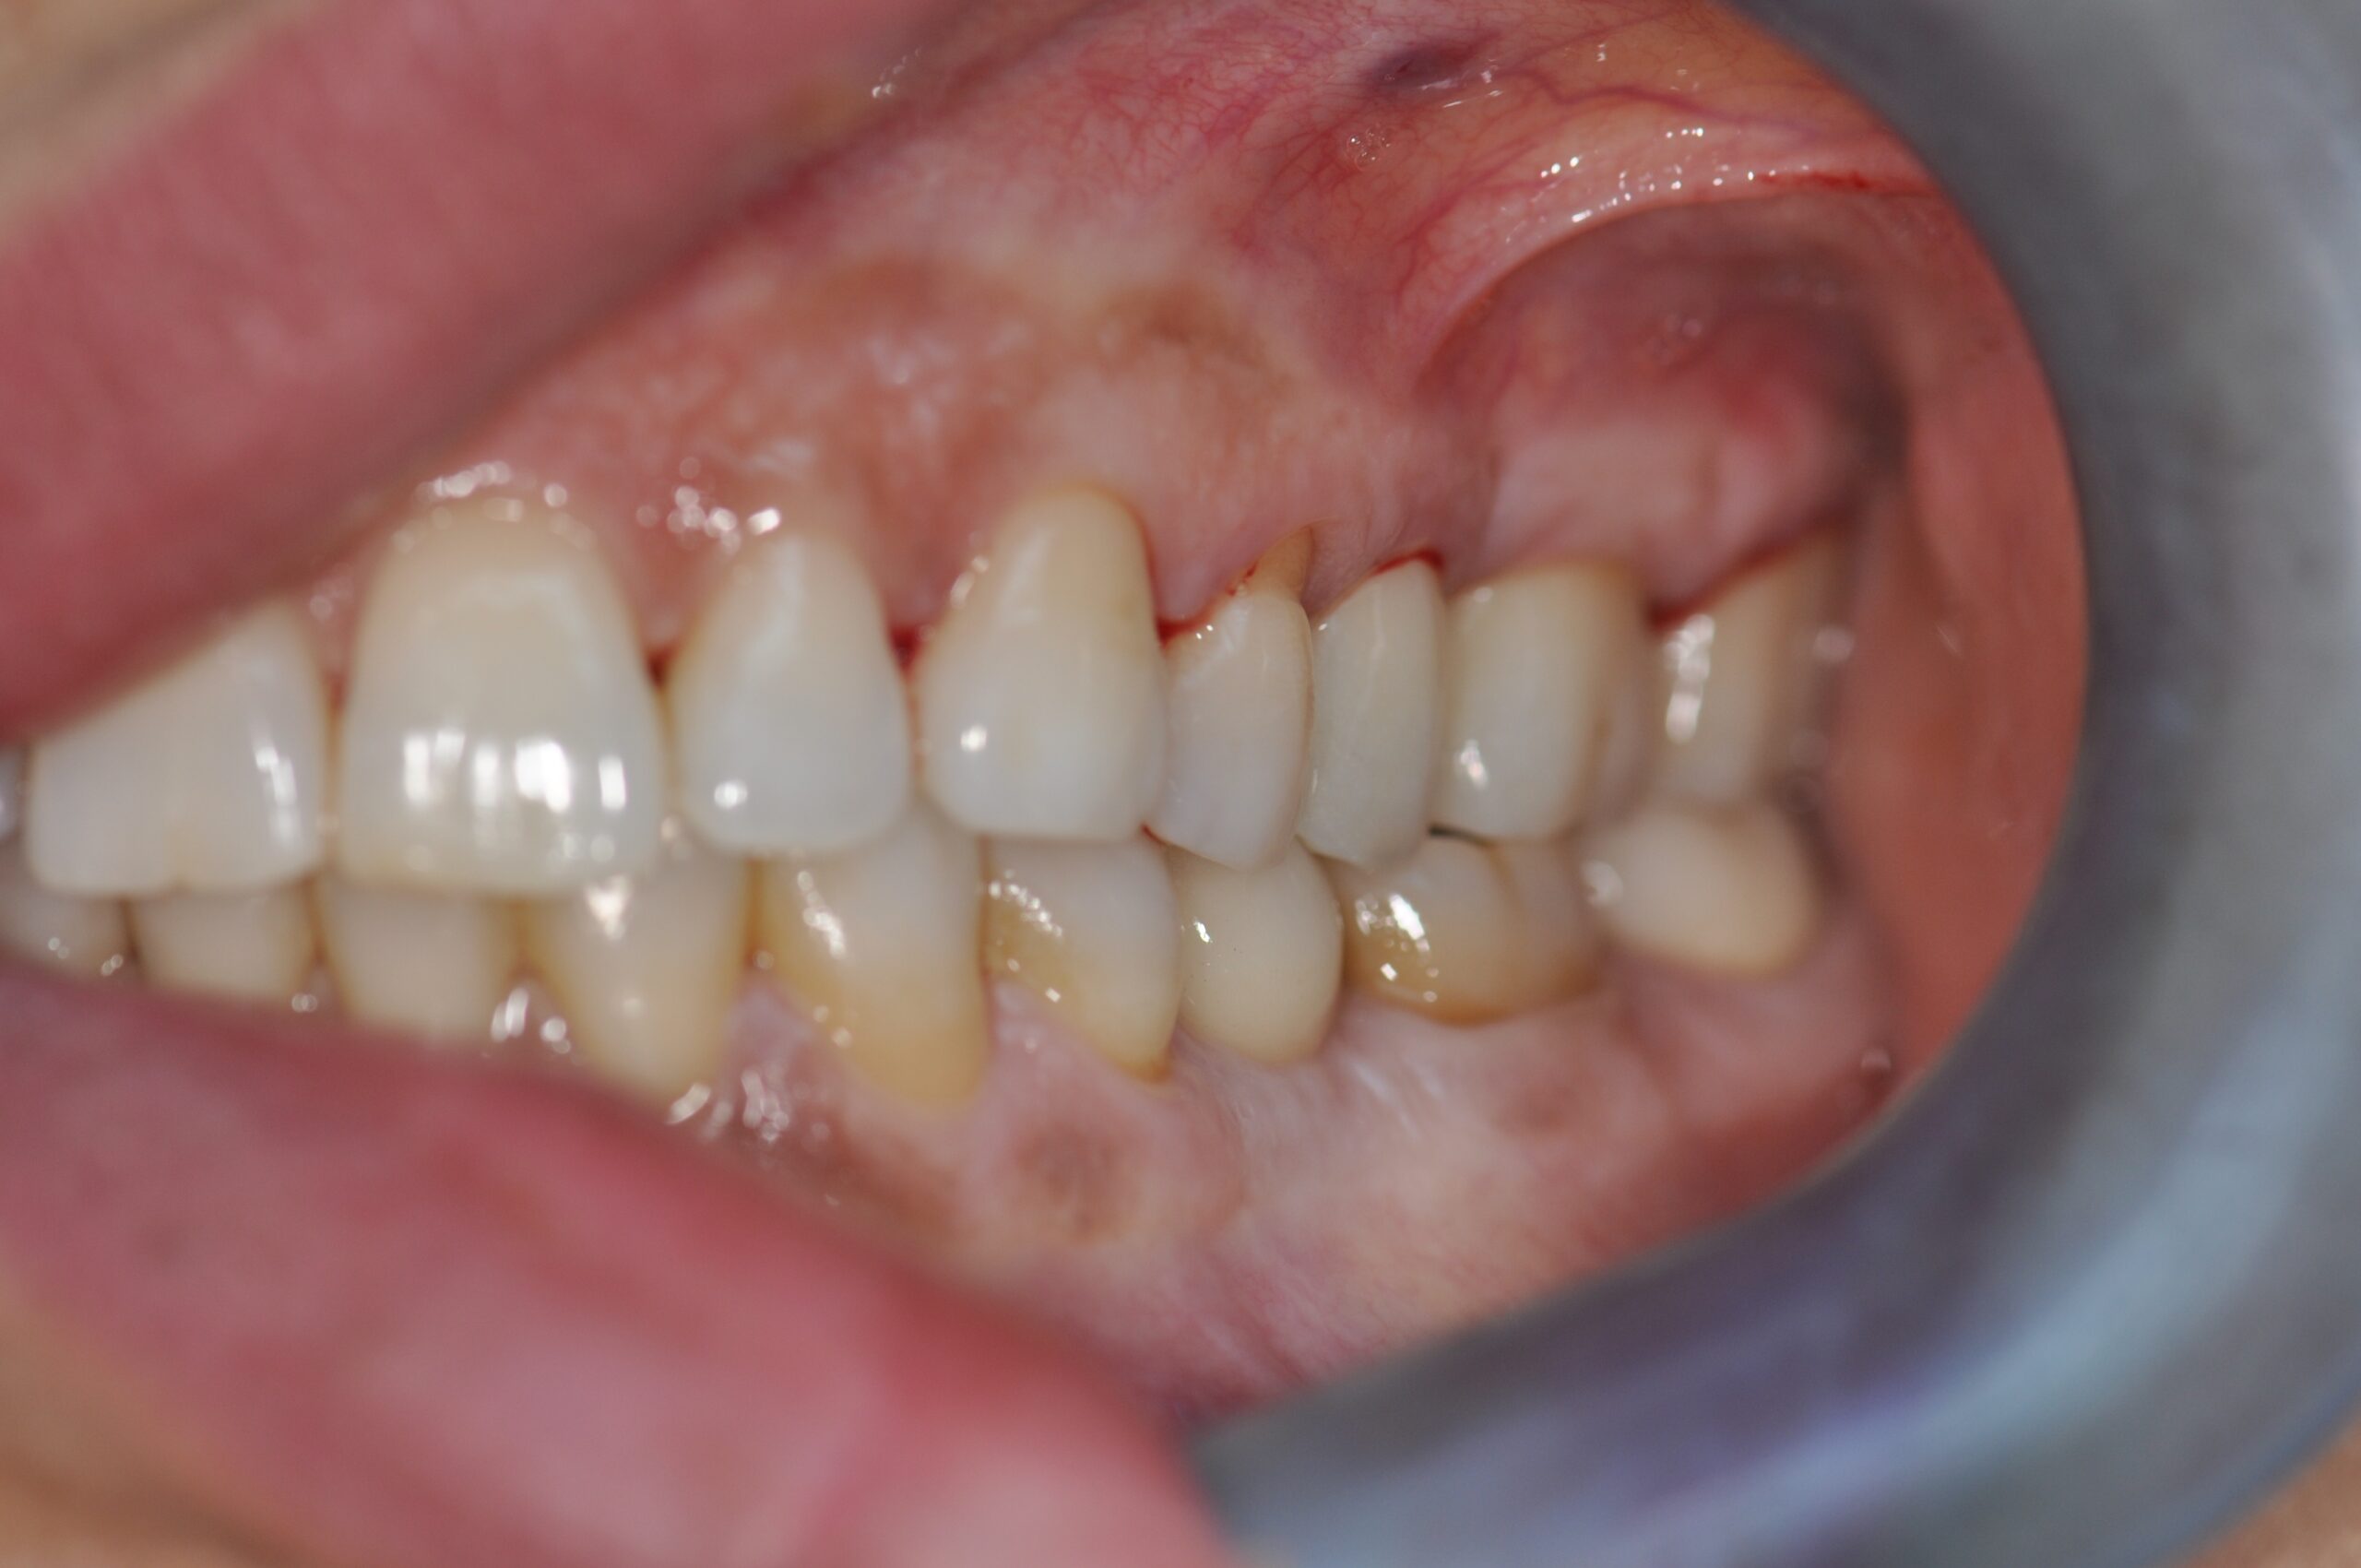

Le sourire gingival est appelé Gummy Smile. Il s’agit d’une situation lors de laquelle la gencive descend trop bas sur les couronnes des dents, soit les parties qui sont normalement visibles lorsqu’on sourit.

Cela se traduit par des gencives proéminentes et des dents qui semblent plus courtes. Bien entendu, cela nuit à l’apparence du sourire.